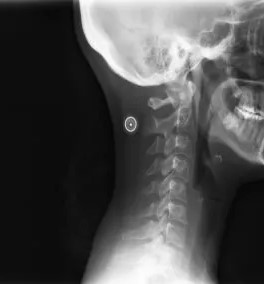

Pracownia wykonuje również zdjęcia odcinka szyjnego kręgosłupa.